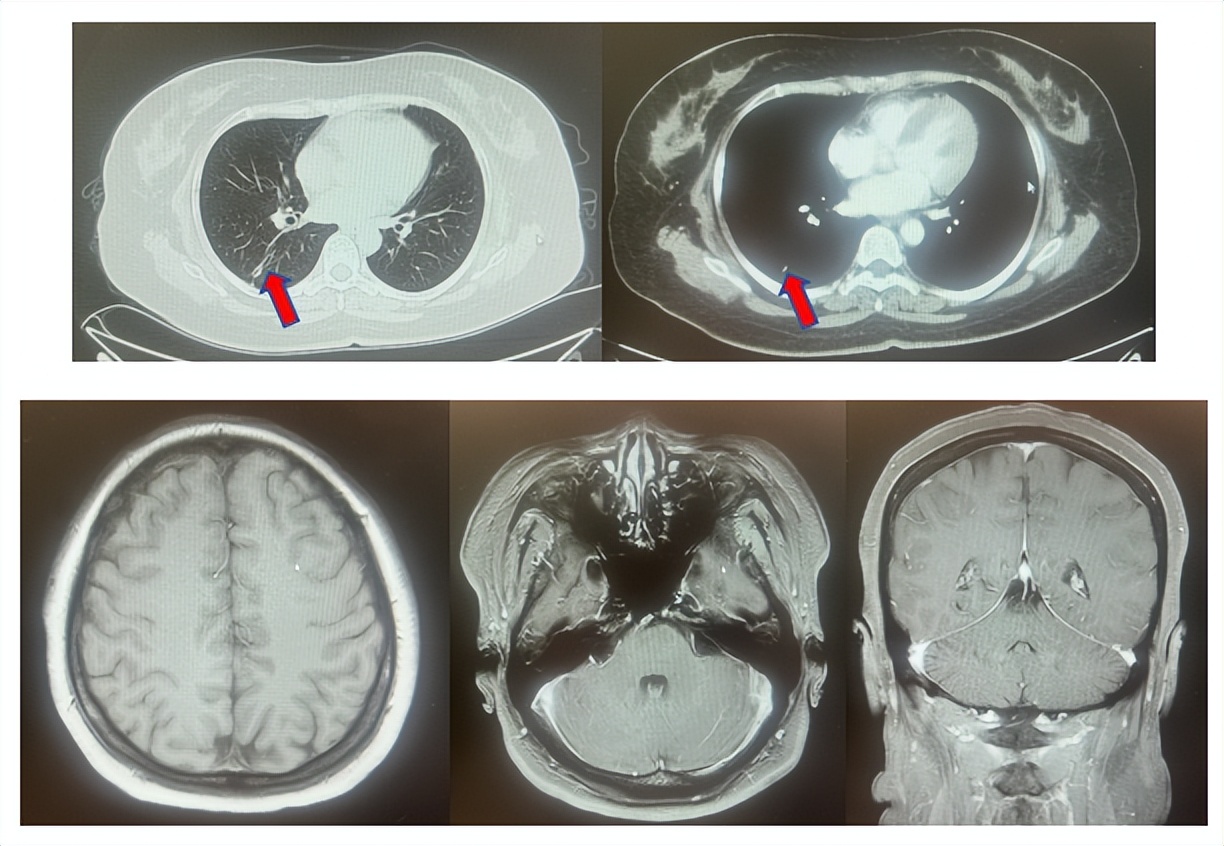

患者符合我科正在开展的“一项比较Durvalumab治疗与标准治疗(含铂化疗)用于PD-L1高表达晚期非小细胞肺癌患者一线治疗的III期随机、开放、多中心研究”的入组要求,经知情同意进入该试验,经随机进入化疗组,于2017年7月至2023年12月应用培美曲塞联合卡铂治疗6周期,后行培美曲塞单药维持治疗105周期,肺内CT现实右肺下叶病灶缩小90%,颅内病灶缩小100%,最佳疗效肺内病灶PR及颅内病灶达CR(图2),于2023年2月复查CT,肺内病灶逐渐增大,至2024年1月,疾病进展出组该临床试验,一线无进展生存为78个月。

图2:上两图分别展示2021年5月患者达到最佳疗效时肺CT肺窗及纵隔窗肺内病灶及肺门淋巴结影像,下三图表示最佳疗效时脑MRI影像

患者进入到二线治疗,该患者再次符合我科“优替德隆对照多西他赛治疗含铂化疗失败的局部晚期或转移性非小细胞肺癌的III期、开放、随机对照临床试验”经随机进入多西他赛组,截止至目前患者已行多西他赛治疗19周期,期间评效为SD(图3),二线无进展生存至今为14个月,患者总生存期截止目前超过92个月(整体治疗过程如图4所示)。

图3:上两图分别展示2024年1月患者一线进展时肺CT肺窗及纵隔窗肺内病灶影像,下两图表示2024年12月患者二线治疗间期评效时肺CT肺窗及纵隔窗肺内病灶影像